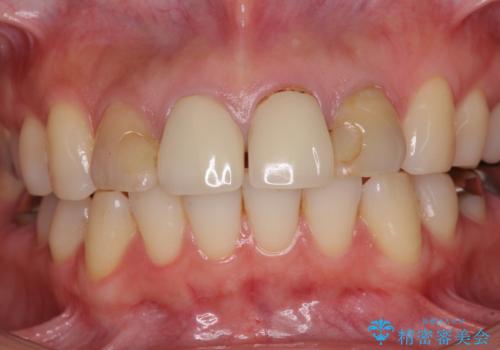

- 前歯のクラウンの変色や歯の変色を気にして来院された患者様です。

グラスファイバーを用いた土台により歯質を強化した上で、オールセラミッククラウンにて補綴することとしました。

統一感があり、歯肉ラインもきれいに整い、清潔感溢れる口元に仕上げることができました。